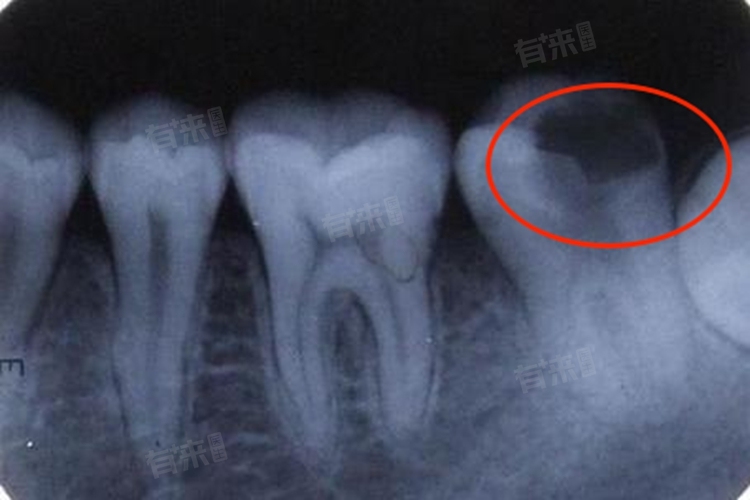

- 根尖片是最基础的牙片类型,主要用于观察单颗牙齿的牙根、根尖周组织及牙槽骨情况,如龋齿深度、根尖周炎、牙周病等。其拍摄范围较小,单次费用在30-60元。该检查操作简便、辐射剂量低(0.005-0.01mSv,相当于一次胸片的1/20),适合常规牙病初筛,如判断智齿是否阻生、补牙前评估牙髓状态等。